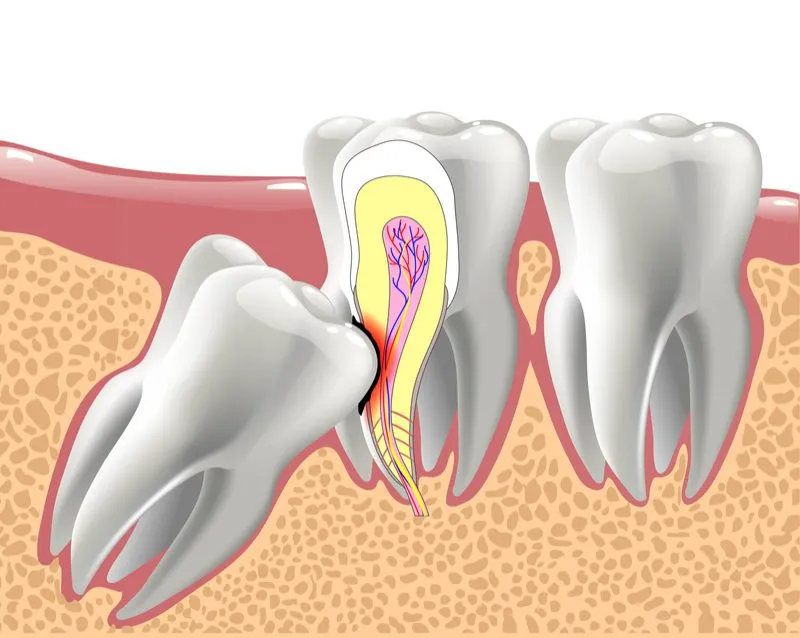

- نهفتگی دندان عقل: گاهی اوقات، دندان عقل به طور کامل رشد نمیکند و زیر لثه گیر میکند. این وضعیت میتواند باعث درد، عفونت و حتی آسیب به دندانهای کناری شود.

در مواردی که دندان عقل نهفته باشد یا رشد ناقصی داشته باشد، نیاز به جراحی دارد. در این روش:

- لثه برش داده میشود.

- دندان در صورت نیاز به قطعات کوچکتر تقسیم شده و سپس خارج میشود.

- محل جراحی با بخیه بسته میشود.